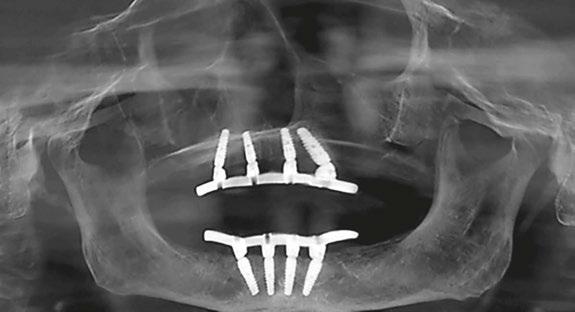

Drs. Dan Holtzclaw, Juan Gonzalez, Aldo Espinosa, Sam Sauza, Raouf Hanna, Peyman Raissi, Chris Epperson, Cory Ryan, Nirjal Patel, Amel Hassan, Peter Fereg, Jumoke Adedoyin, and Dan Fenton report on

4 Implant Practice US Volume 16 Number 2 TABLE OF CONTENTS SERVICE PROFILE The Advanced Dental Implant Center Network builds momentum 32 GOING VIRAL Is social media placing your personal privacy or your small business at risk? Mark Pribish offers guidance on minimizing risks of social media 34 PRODUCT PROFILE Diet, nutrition, and the implant patient Dr. Thomas J. Balshi discusses how key nutrients affect implant success ............................................. 36 PRODUCT PROFILE Cool Jaw® hot/cold therapy ....................................... 38 PRODUCT PROFILE The OsteoGen® Plug: one-step bone grafting solution for socket preservation without a membrane! ............................. 40 Connect. Be Seen. Grow. Succeed. | www.medmarkmedia.com READ the latest industry news and business WATCH DocTalk Dental video interviews with KOLs LEARN through live and archived webinars RECEIVE news and event updates in your inbox by registering for our eNewsletter CONNECT with us on social media www.implantpracticeus.com 26 CONTINUING EDUCATION Pterygoid implant survival rates with full-arch immediate-loading protocols

survival rates and

pertinent data *Paid subscribers can earn 4 continuing education credits per issue by passing the 2 CE article quizzes online at https://implantpracticeus.com/category/continuing-education/